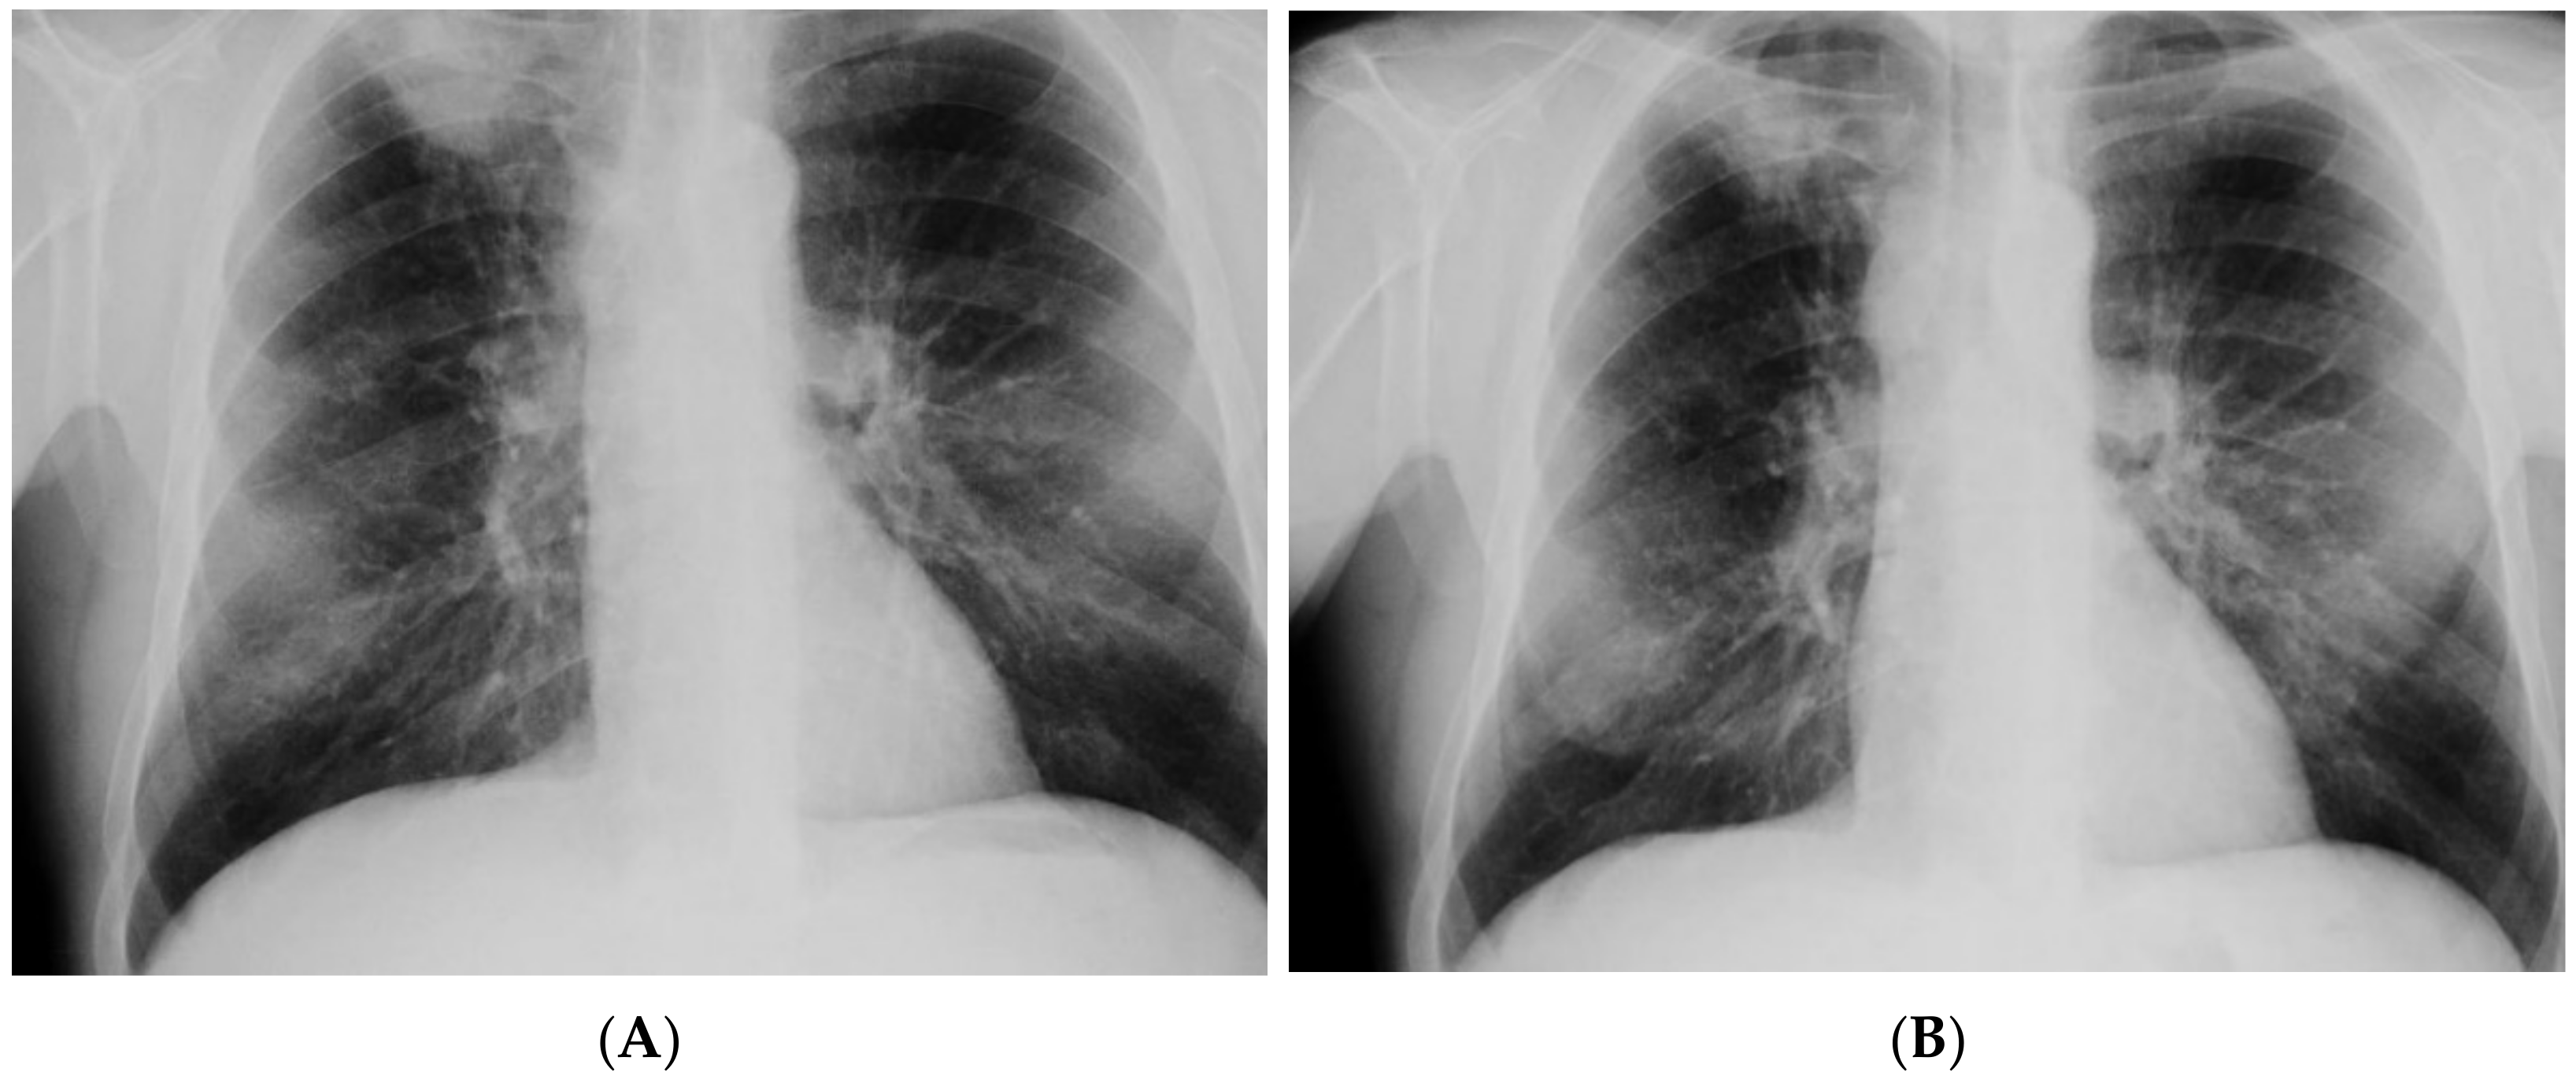

| Imaging studies during antimycobacterial treatment | Chest X-ray: After 2 mo of treatment—an irregular infiltration in the upper area of the right lung (Figure 2A). After 5 mo of treatment—reduced infiltration (Figure 2B) Chest CT: After 5 mo of treatment an oval nodular lesion with calcification, enlarged right and left mediastinal nodes, nodular lesions in the lungs (Figure 3A,B) | Chest X-ray: No improvement by radiographic criteria after 17 mo of treatment (Figure 5B). Still no improvement by radiographic criteria after further 2 years of treatment (Figure 5C) Chest CT: An extensive cavity in the upper lobe of the right lung, infiltrative lesions in the middle lobe, cavernous lesions in the left lung (Figure 4) |